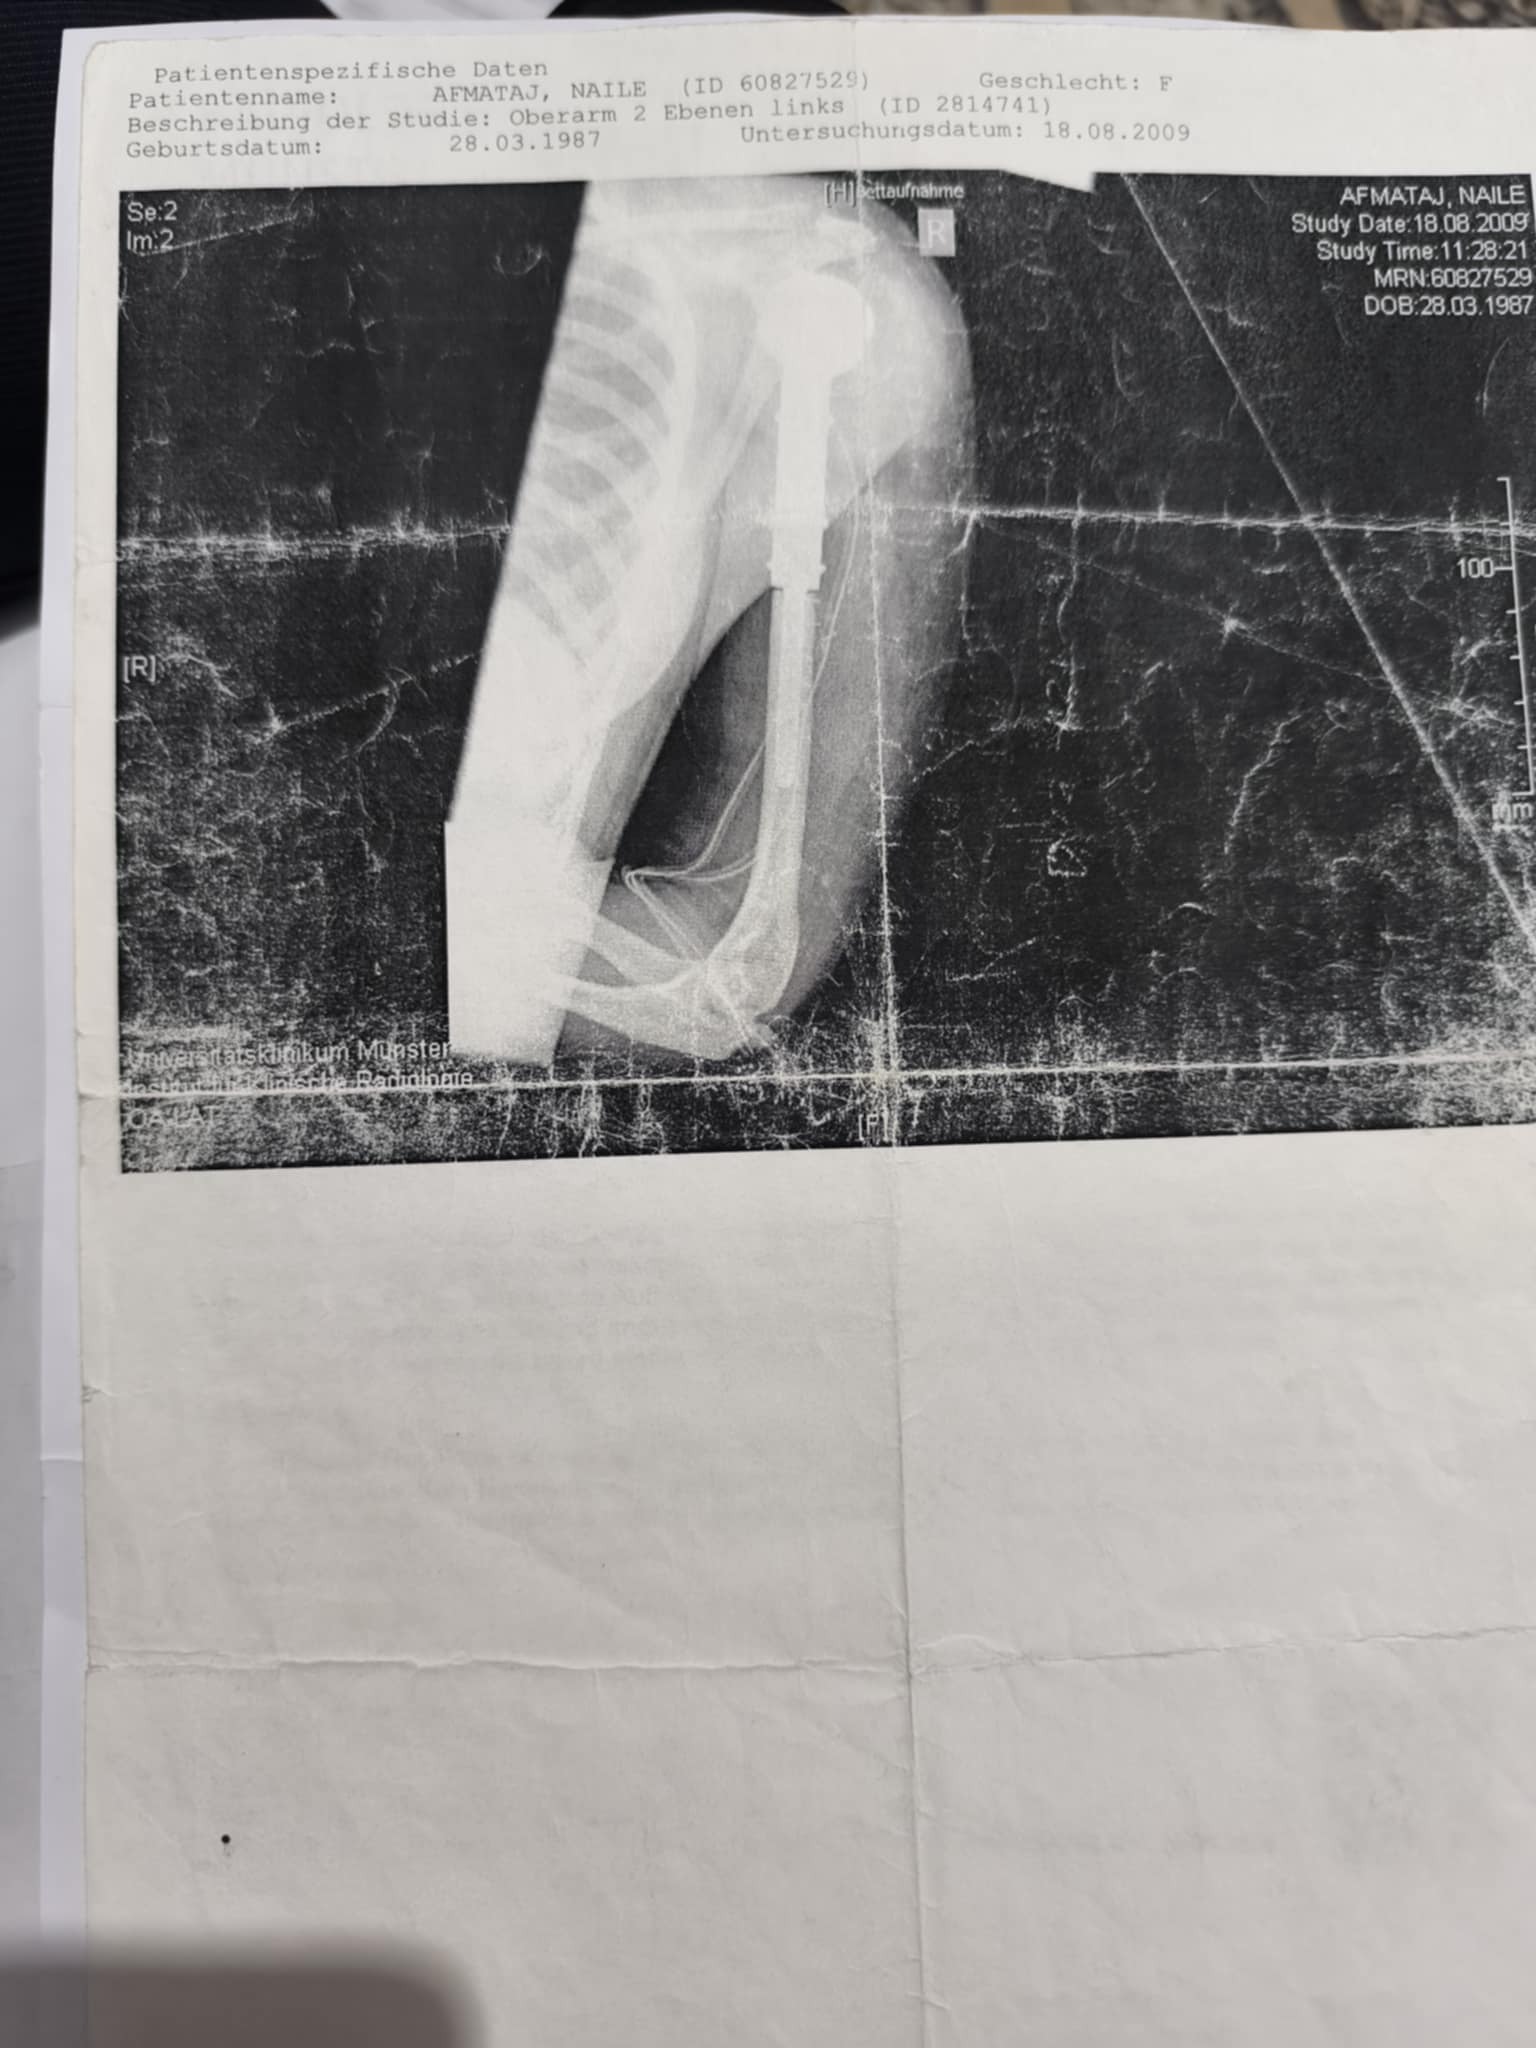

Es handelt sich um eine vierfache Mutter Naile Afmataj (Albanien) , die im Jahr 2009 aufgrund eines bösartigen Tumors im Oberarm in Deutschland operiert wurde. Damals wurde der betroffene Knochen durch eine künstliche Platte ersetzt. Um die Operation zu ermöglichen, hatte ihr Ehemann sein Haus verkauft.

Seit etwa zwei Monaten leidet die Frau unter starken Schmerzen im Oberarm. Eine aktuelle Nachuntersuchung in der Uniklinik Münster (UKM) ergab, dass die künstliche Schulter instabil ist und dringend operiert werden muss. Der Oberarzt hat eine zeitnahe Operation dringend empfohlen, da eine drohende Infektion lebensbedrohlich für die Patientin sein könnte.